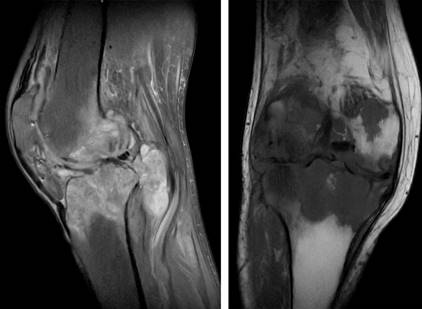

Tres meses previos a nuestro contacto, se realizó resonancia magnética (RM) con datos de proceso inflamatorio difuso sobre estructuras óseas, condrales, ligamentarias, tendinosas, musculares y cápsula articular; múltiples lesiones osteocondrales en compartimento patelofemoral, femorotibial, menisco lateral y medial; quiste de Baker (Figuras 1 y 2).

Figura 1: Resonancia magnética nuclear de rodilla derecha con datos inflamatorios difusos, múltiples lesiones osteocondrales, quiste de Baker y datos sugestivos de osteomielitis.